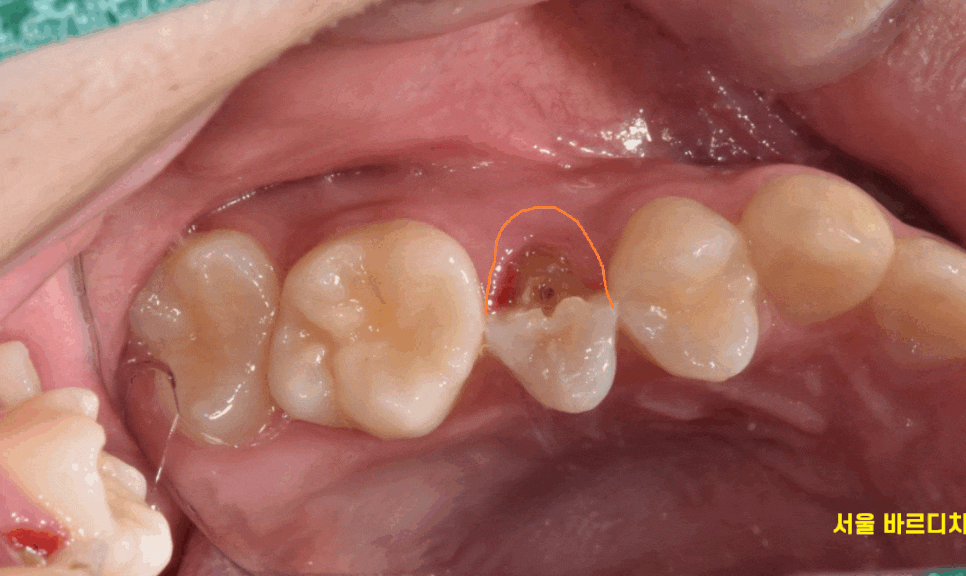

치아가 골절됐어요

급하게 치아가 세로로 골절 되었다고

강일동 치과에 연락을 주신 환자분입니다.

정확히 치아가 절반으로 나누어졌습니다.

치아가 쪼개지기도 하고

치아 골절 발생